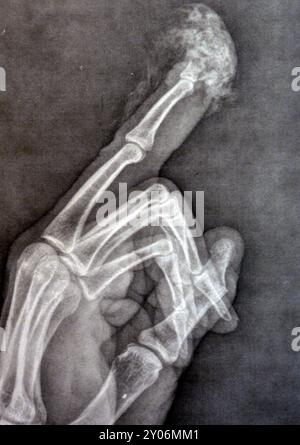

Plain X-Ray reveals distal tip amputation of distal phalanx of the

Plain X-ray Reveals Distal Tip Amputation Stock Photo 2499162053